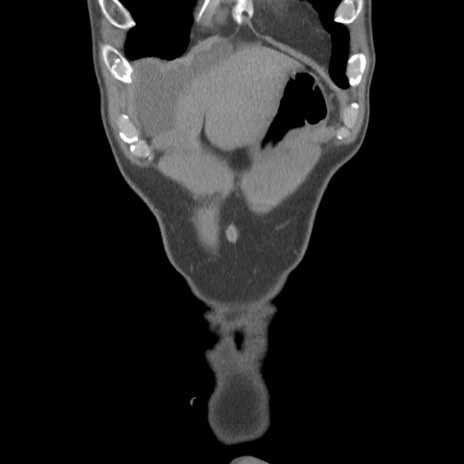

症例56 CT(冠状断像)